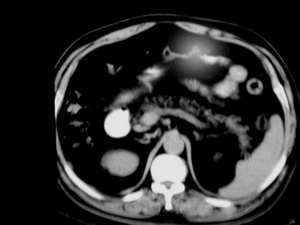

标题: CT2418:求诊:无痛性黄疸10天,无发热。

男,70y,就是单纯无痛性黄疸

胆囊内结石,胆管扩张,胆总管壁不厚,单从征象考虑,未见明显肿物.不过年龄70应该做mrcp进一步确诊.除外占位病变.

结合胆囊结石,高度怀疑胆总管结石。

胆总管结石可能